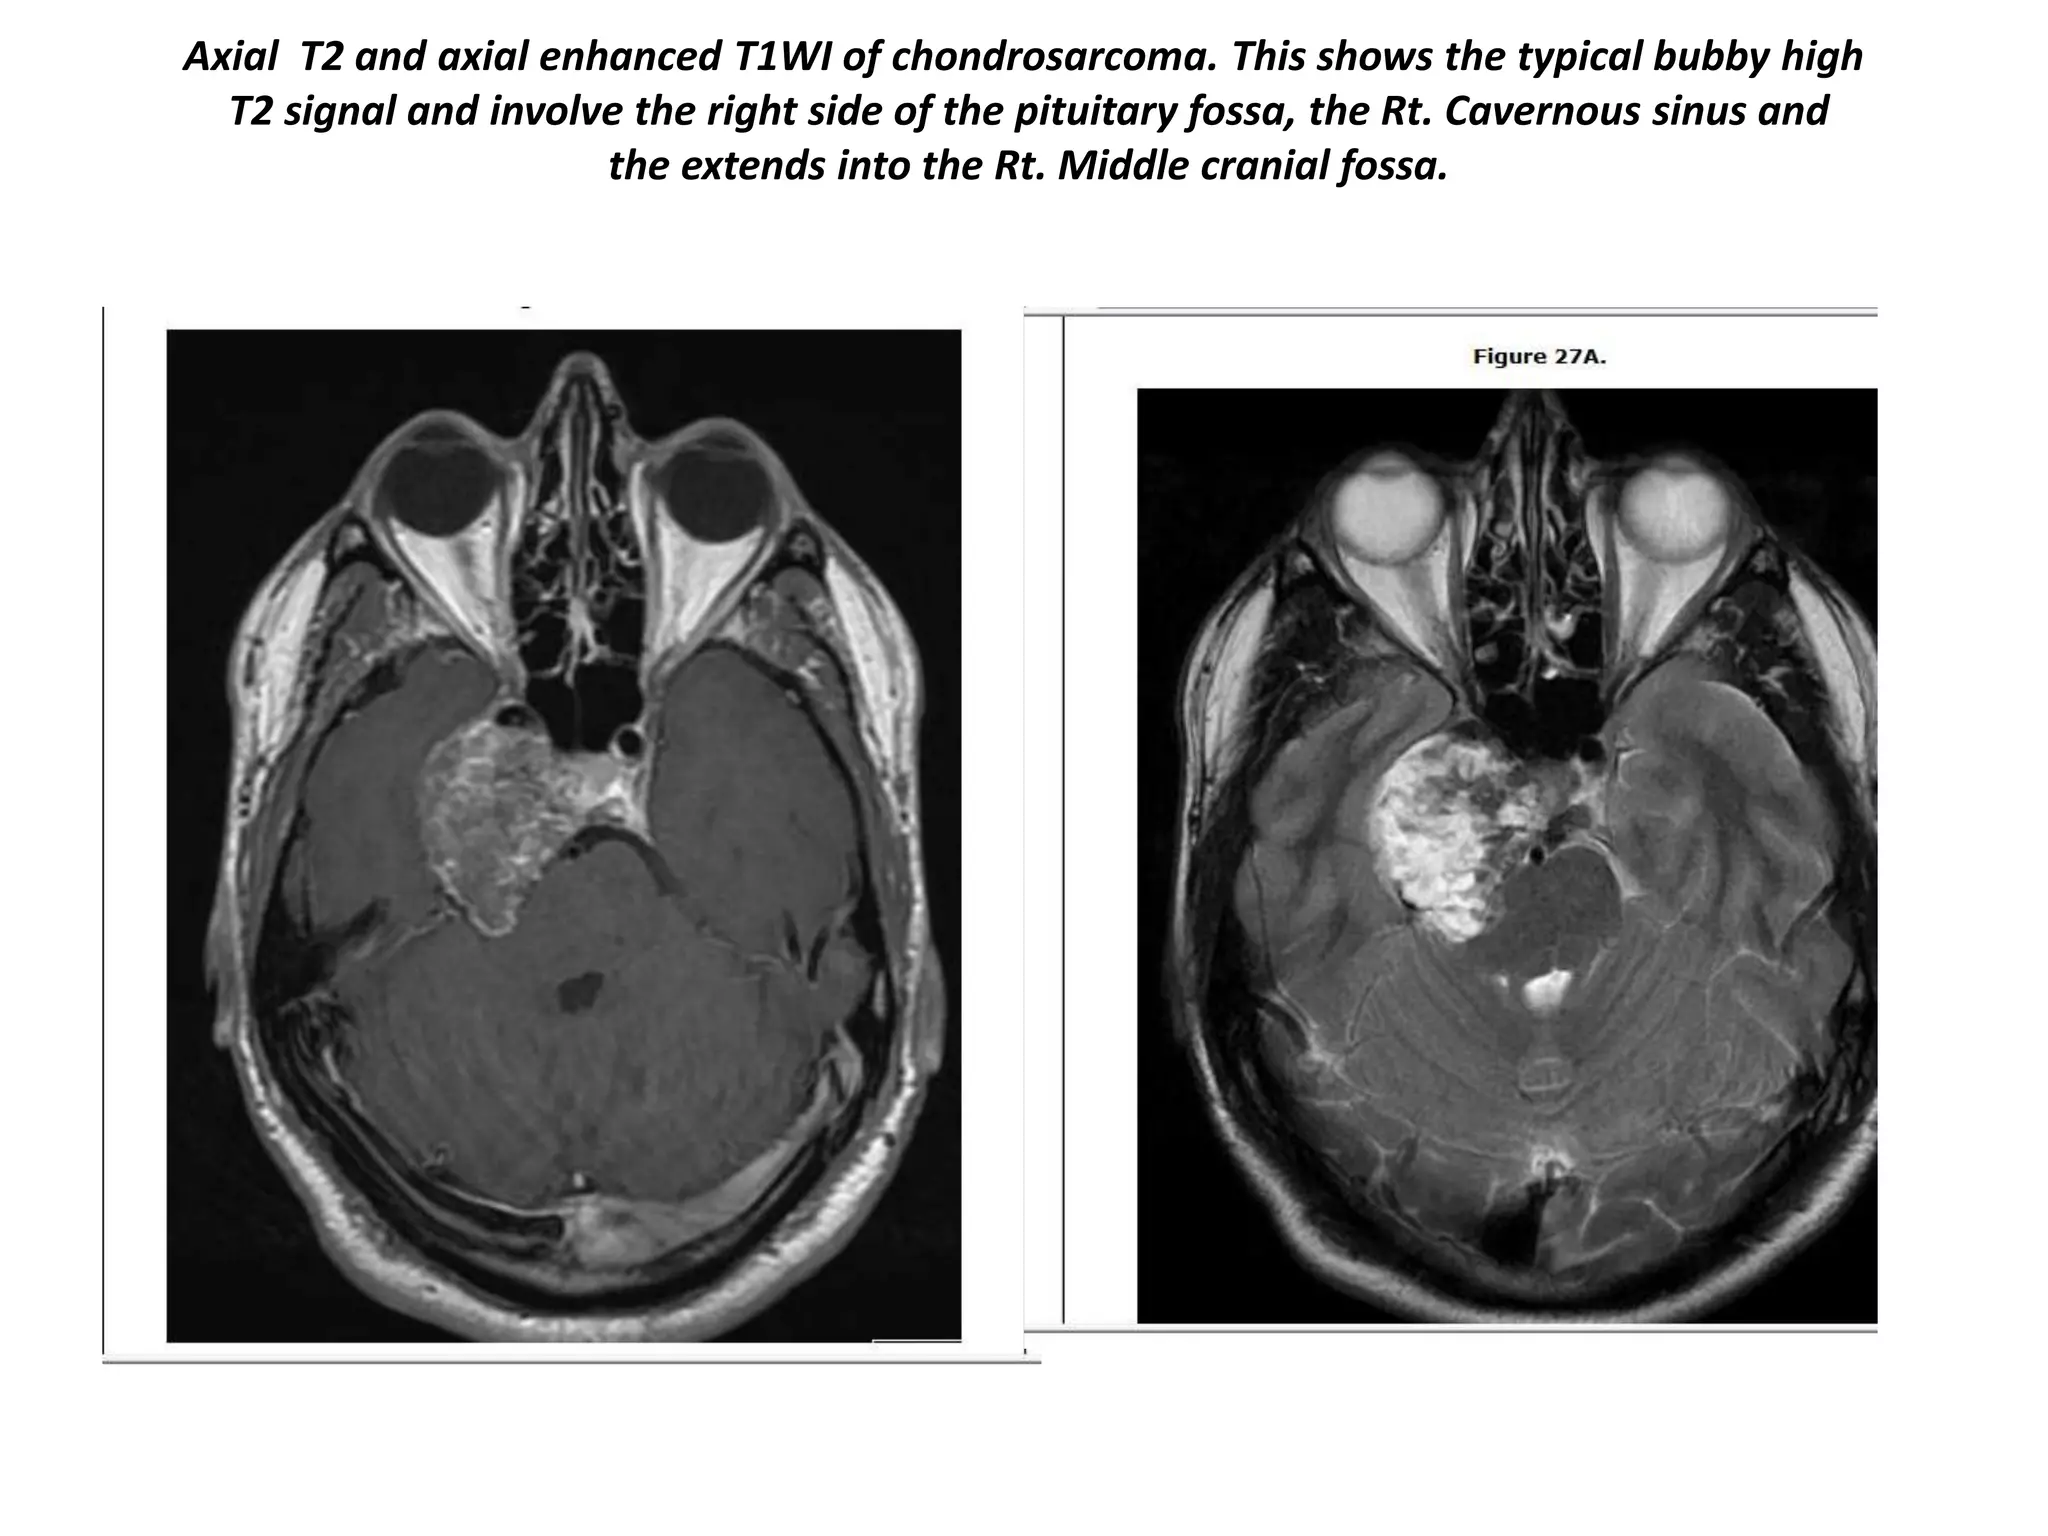

Axial T2 and axial enhanced T1WI of chondrosarcoma. This shows the typical bubby high

T2 signal and involve the right side of the pituitary fossa, the Rt. Cavernous sinus and

the extends into the Rt. Middle cranial fossa.

Axial T2 andaxial enhanced T1WI of chondrosarcoma. This shows the typical bubby high T2 signal and involve the right side of the pituitary fossa, the Rt. Cavernous sinus and the extends into the Rt. Middle cranial fossa.